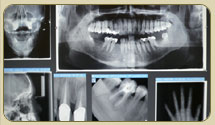

Digital Radiology

All x-ray images including all intra-oral radiographs & panoramics

are in a digital format, viewed on a computer screen and thus requiring

less than one third of the radiation doses as compared with a conventional

X-ray film.